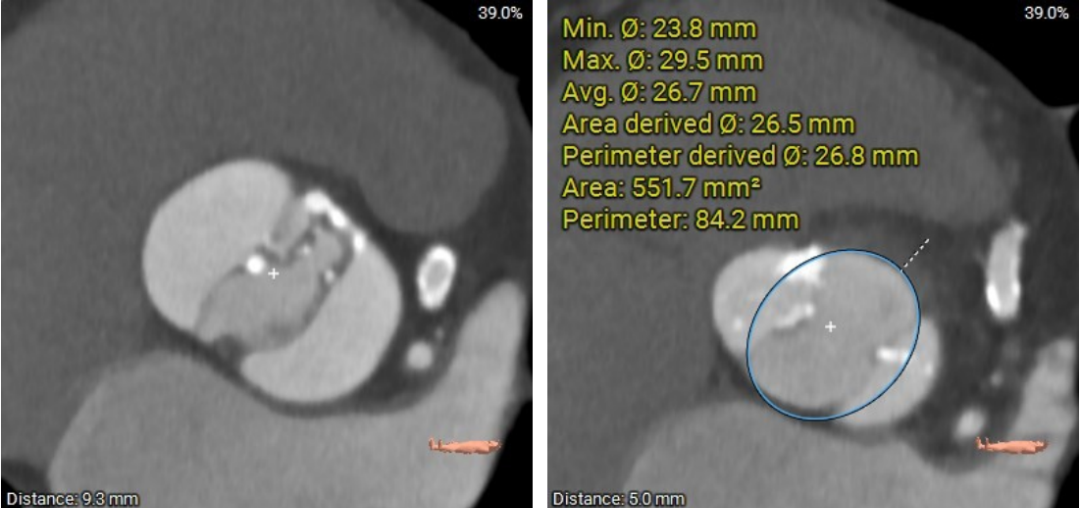

瓣环及左室流出道:

主动脉瓣的开口面积的估计(在瓣环平面5mm 以上测量):